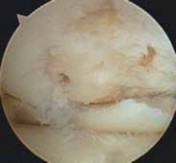

2. Chondroplasty or marrow stimulation is now performed. If the osteotomy is being performed together with a cartilage restorative procedure (eg, autologous chondrocyte implantation), the osteotomy is performed first and then the restorative cartilage procedures are performed, to minimize any trauma to the newly implanted pe-riosteal covering or injected cartilage cells. TECH FIG 1 • A. Arthroscopic image of the medial compartment. Note the bone exposed on the medial femoral condyle and tibia. B. Arthroscopic image following use of a microfracture technique. On entering the lateral compartment, an unexpected cartilage lesion was found on the lateral femoral condyle. Offloading the mechanical axis into the lateral compartment that already is degenerated is a

A B contraindication to the procedure.